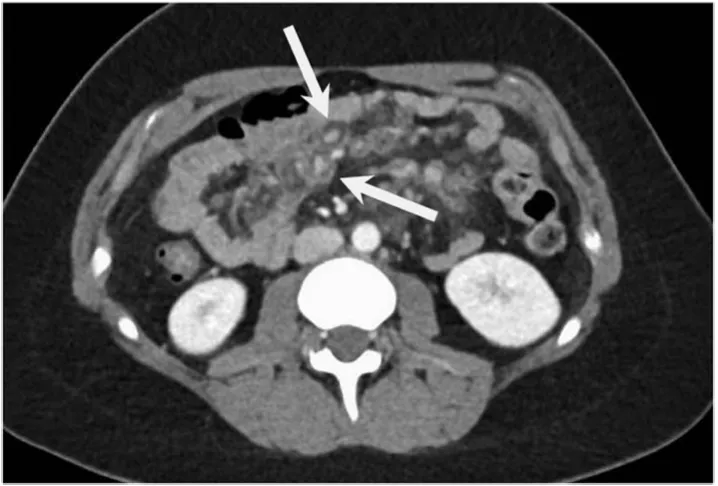

增强CT一扫,医生倒吸一口凉气:肠系膜上出现了“靶环状”强化病灶,周围全是浑浊的脂肪条索(图1)。

图1.腹部CT显示环靶征及脂肪条索影